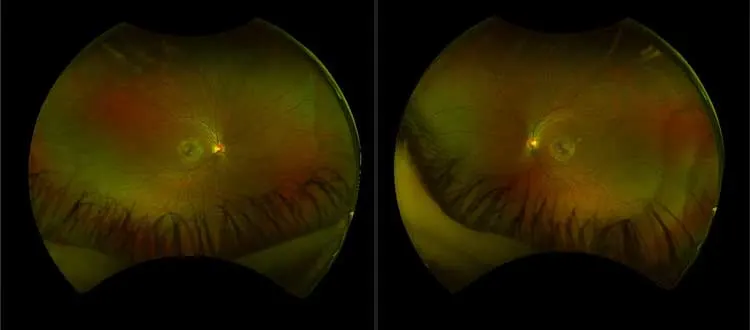

Stargardt’s or macular dystrophy refers to a set of hereditary progressive degenerative eye diseases that primarily affect the macula of the retina thereby causing gradual loss of central vision. For the people diagnosed, the task of moving from the point of diagnosis to that of proper management is often quite a challenging process riddled with